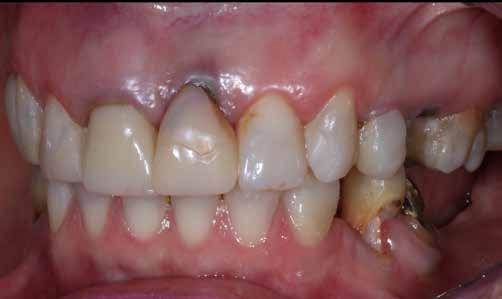

A rendelésünkön jelentkező 40 éves nőbeteg a mosolyának esztétikai megjelenésén szeretett volna javítani (1. ábra)

A vizsgálat során a jobb felső első kisőrlőfog (1,4) és a bal felső első kisőrlőfog (2.4), valamint a köztük elhelyezkedő fogak kifejezett mértékű kopását észleltük (14-24). Ezen felül a felső metszőfogak (1.2–2.2) élei egyenetlen lefutással rendelkeztek, és a jobb felső nagymetszőfog (11) – amelyet korábban gyökérkezeltek és kompozit töméssel láttak el –jelentős színbeli eltérést mutatott. Az 1.4-es és 2.4-es fo-

A 26 éves férfi páciens azzal a kéréssel kereste fel a rendelőnket, hogy a frontfogai esztétikusabb megjelenését szeretné elérni. A páciens jó általános egészségi állapottal rendelkezett, nem szenvedett allergiáktól és nem kellett rendszeresen gyógyszereket szednie. A páciens lehetőség szerint kerülte a fogai megmutatását. Rendkívül zavarónak találta a nagymetszői között, a középvonalnak megfelelően látható rést, a fogain látható kopási jeleket, valamint a fogai méretét is túl kicsinek találta. A szájüregi vizsgálat során megállapítottuk, hogy a nagymetsző fogai (11, 21) élharapásban vannak, valamint az alsó fogíven kismértékű torlódást észleltünk. A felső frontfogakon

(13-23) attrícióra utaló jeleket találtunk. A fogak kopása a nagymetszőfogaknak megfelelően volt a legkifejezettebb (1. ábra) . Az előbbiekben említett fogak (11, 21) ezen kívül némileg elfordultak, és jelentősebb méretű diasztéma volt köztük. A páciens Angle I.-osztályú állcsontrelációs helyzettel rendelkezett. A vizsgálat során feltűnt, hogy a páciens csak nagyon óvatosan mert mosolyogni (2. ábra)